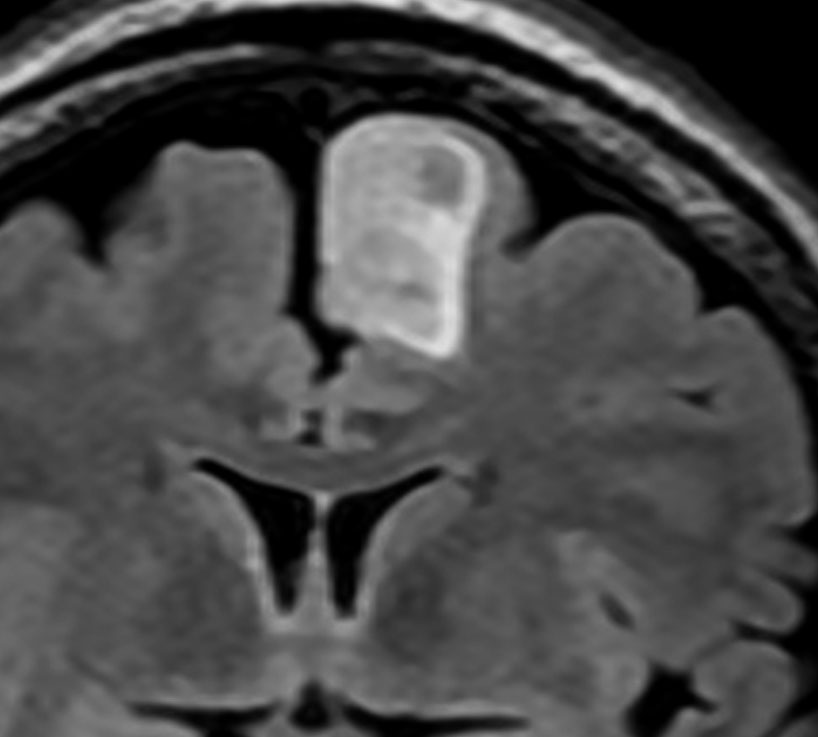

T2-FLAIR mismatch sign (T2とフレアの信号が違うこと)

protoplasmic astrocytomaに特徴的なMRI所見です。T2強調画像(左側)では白く(強い均一な高信号)見えます。でもフレア画像(右側)では白く縁取ったように見えます。びまん性星細胞腫の大きな特徴とされます。内部がとても柔らかいドロドロした腫瘍のこともあります。

mucoid degenerationを含むprotoplasmic astrocytomaの像です。グレード2の典型的病理像です。